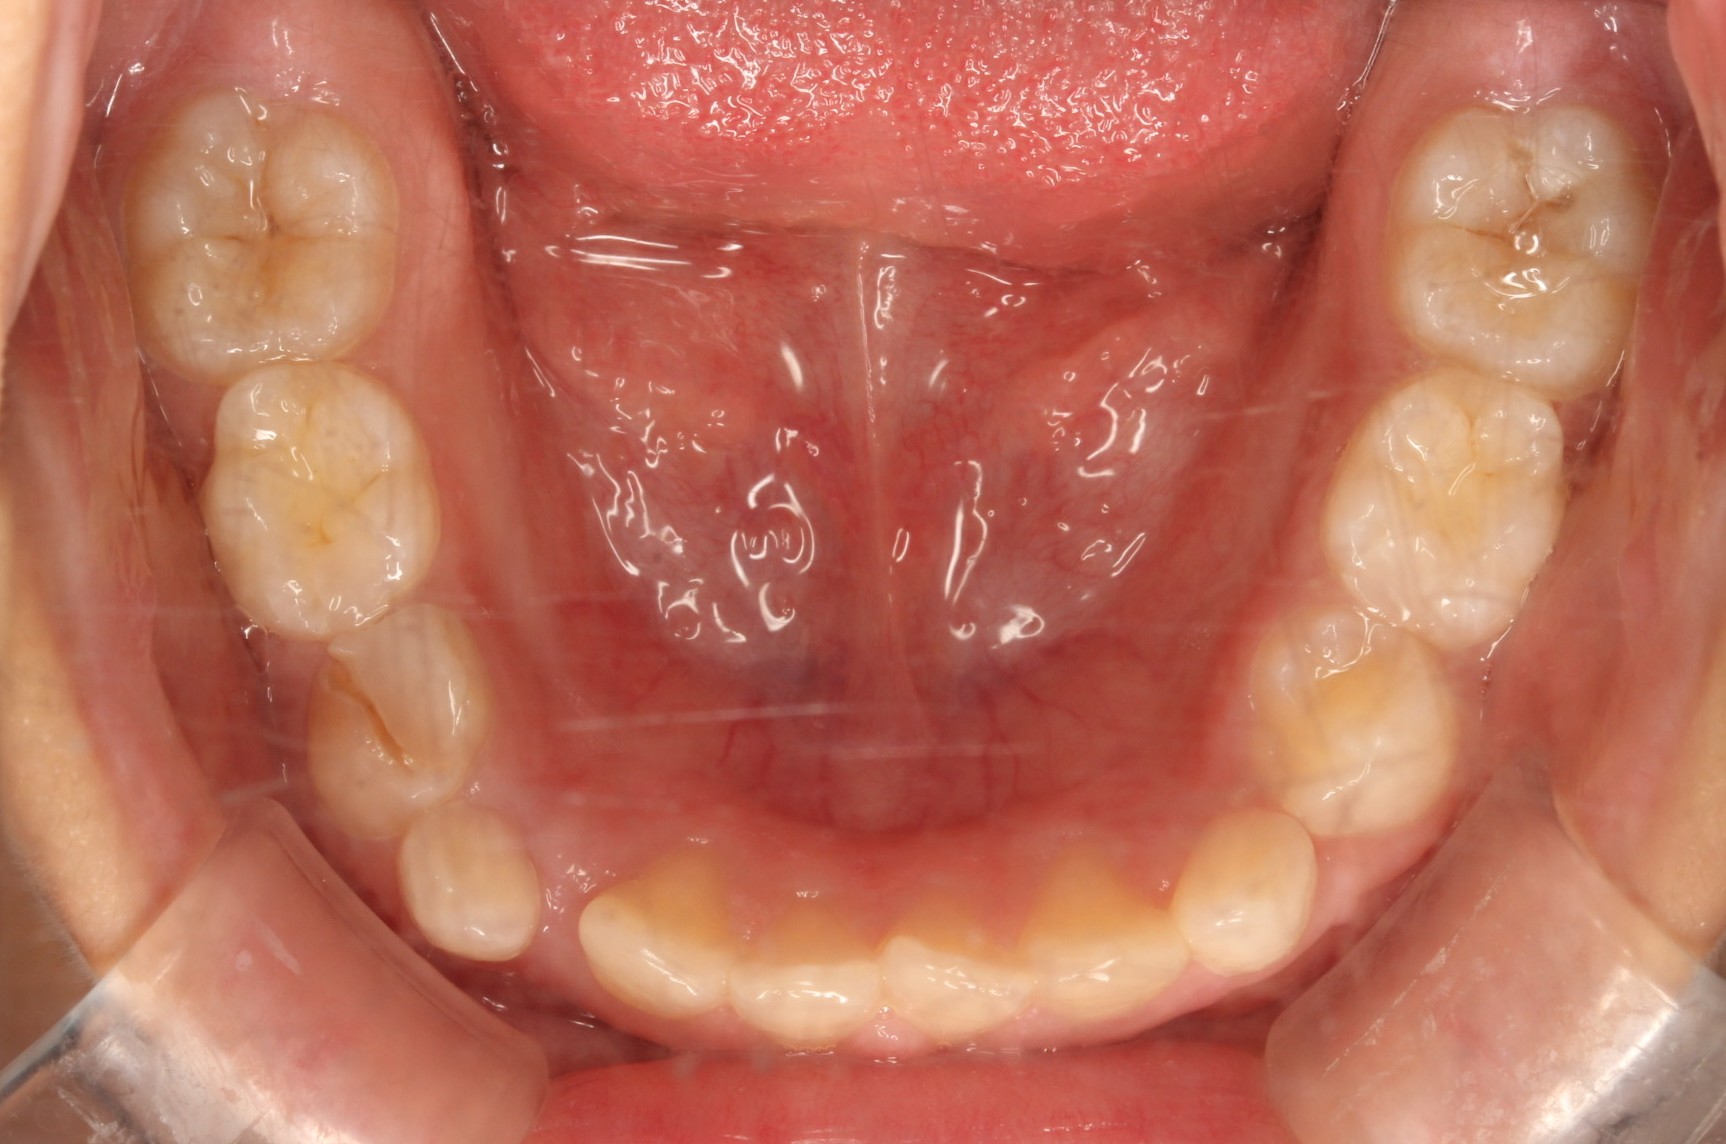

矯正術前:上顎

矯正術前:下顎